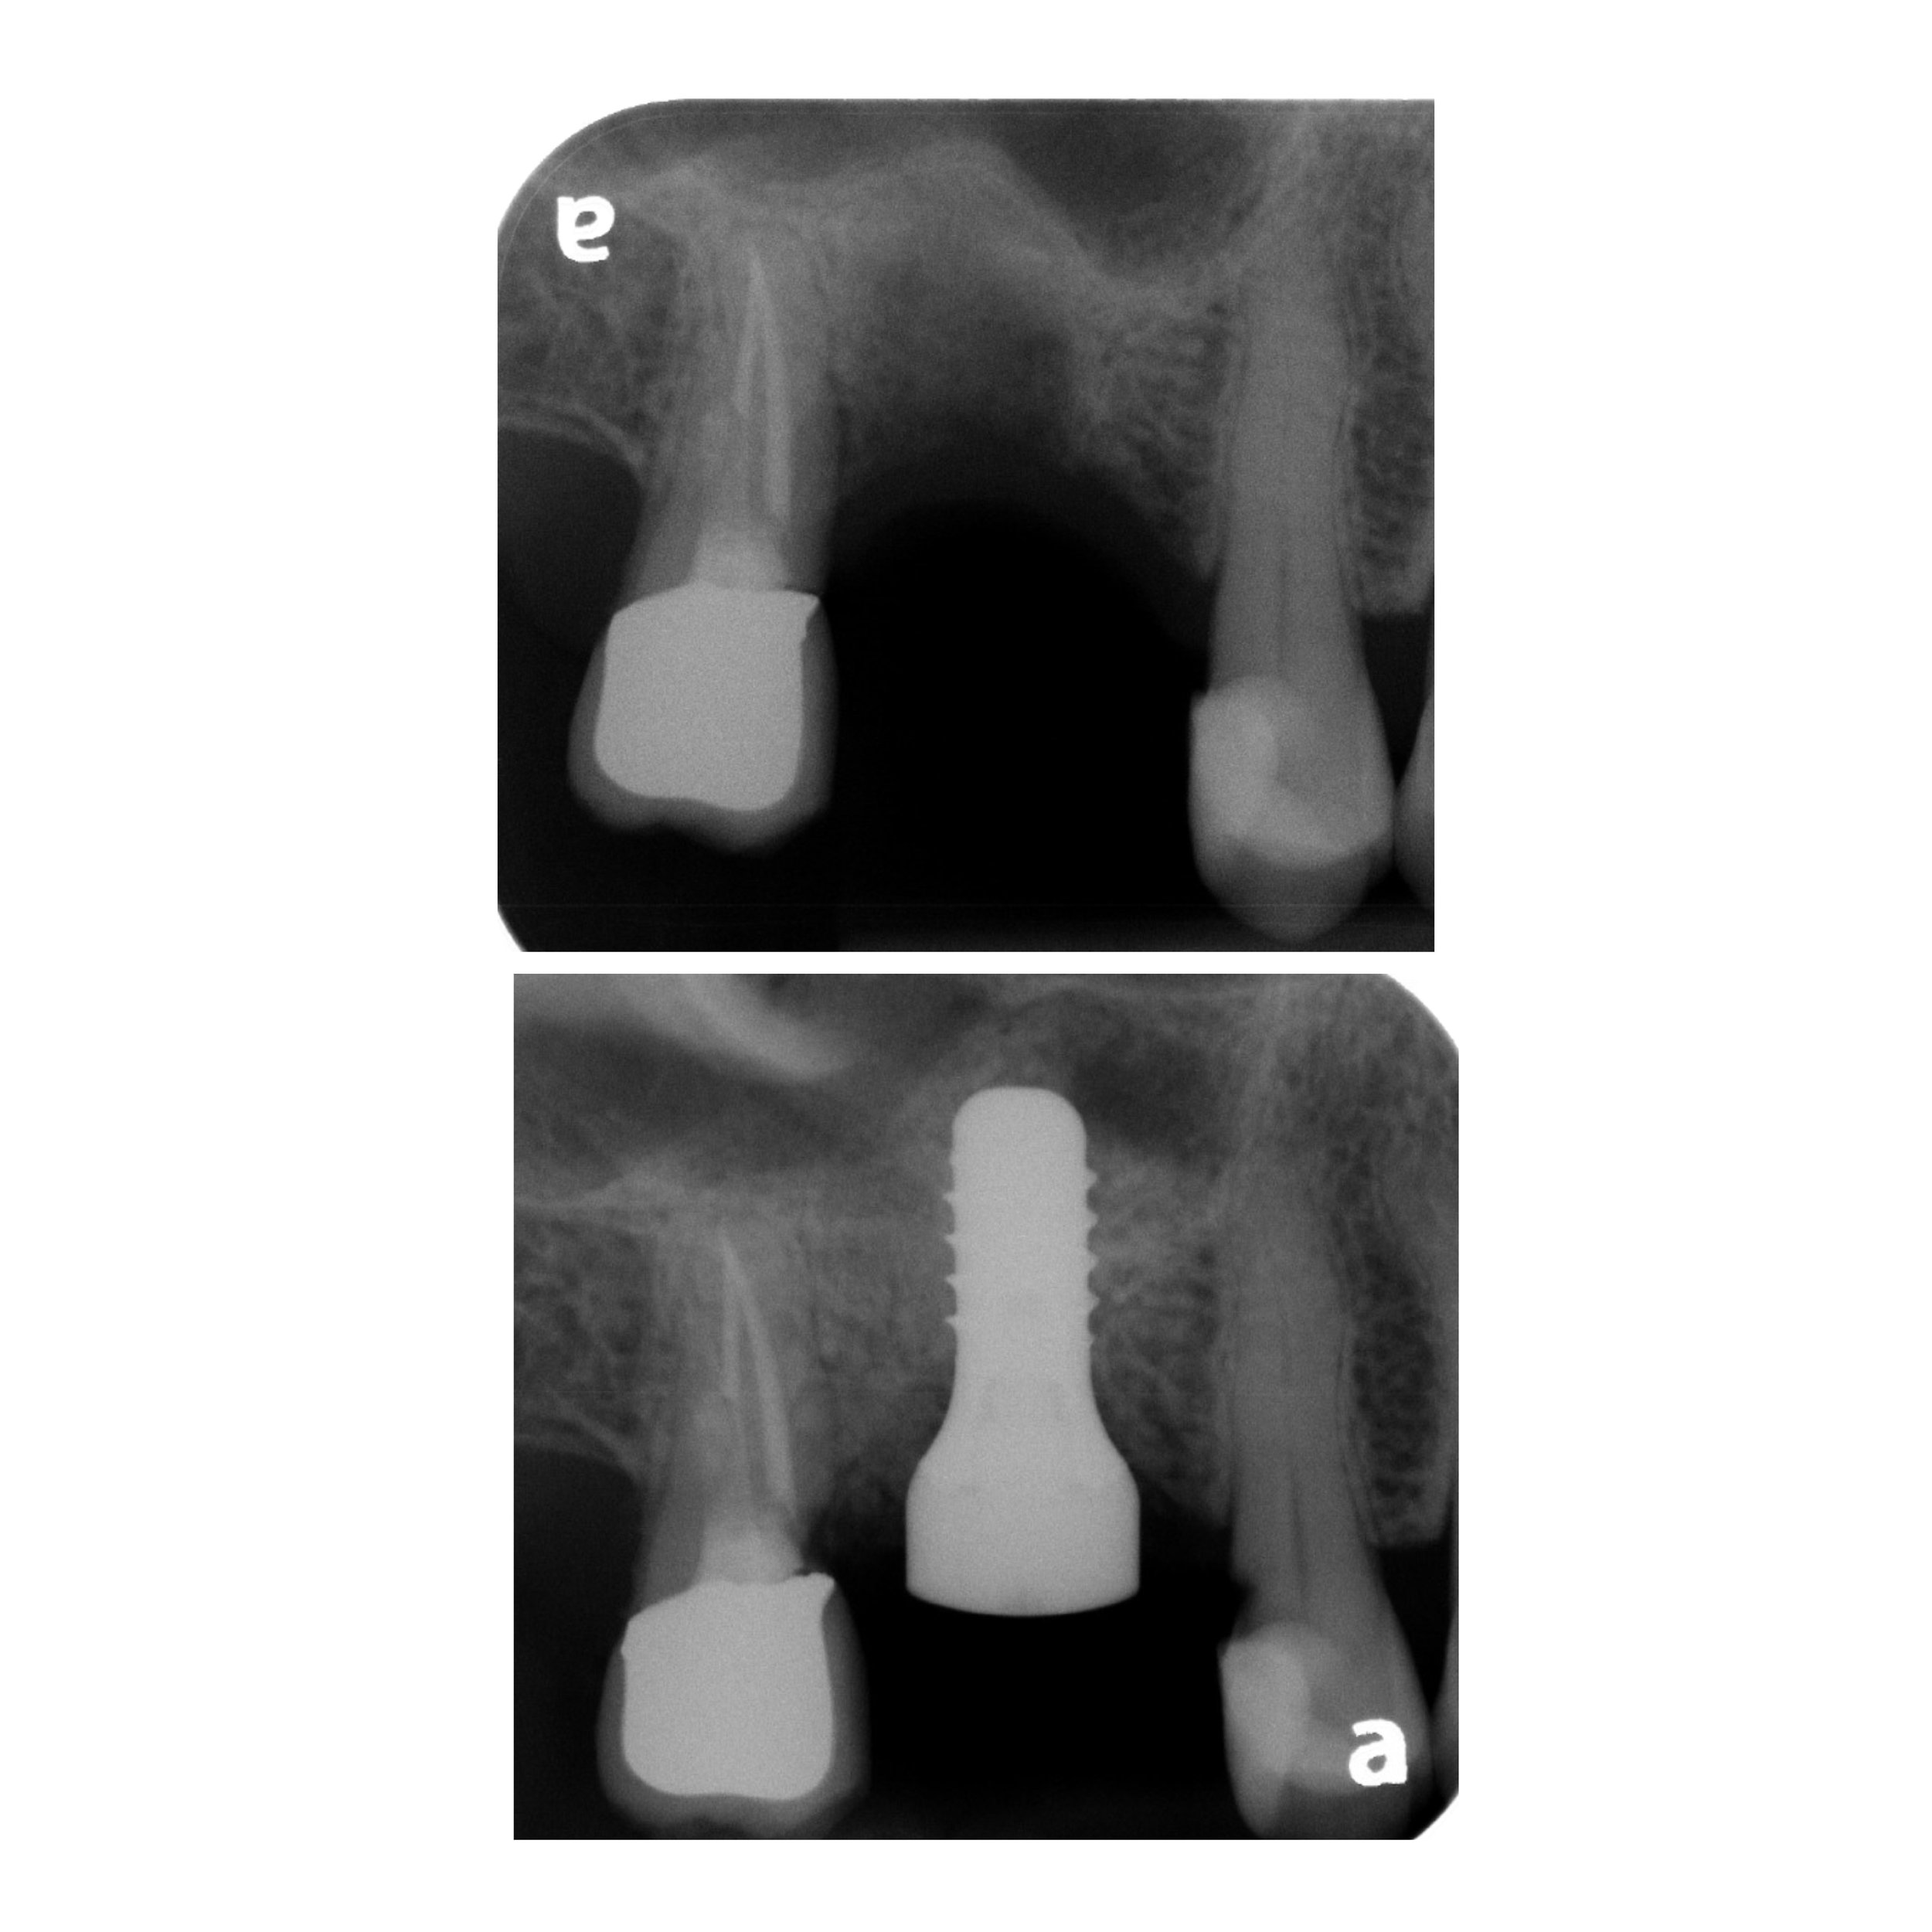

The most common application for an implant is replacing a single missing tooth. Unlike a bridge, an implant does not require the "grinding down" of healthy adjacent teeth.

• The Component: A medical-grade titanium post acts as a synthetic root.

• The Benefit: It prevents the surrounding teeth from shifting and stimulates the jawbone to prevent bone loss.

• The Result: Once healed, your general dentist places a custom crown that looks, feels, and functions like a natural tooth.

3. Integration (Osseointegration): We allow a healing period for the bone to fuse with the implant.

4. Final Restoration: Your general dentist takes over to design and fit your final crown, hybrid, or overdenture.